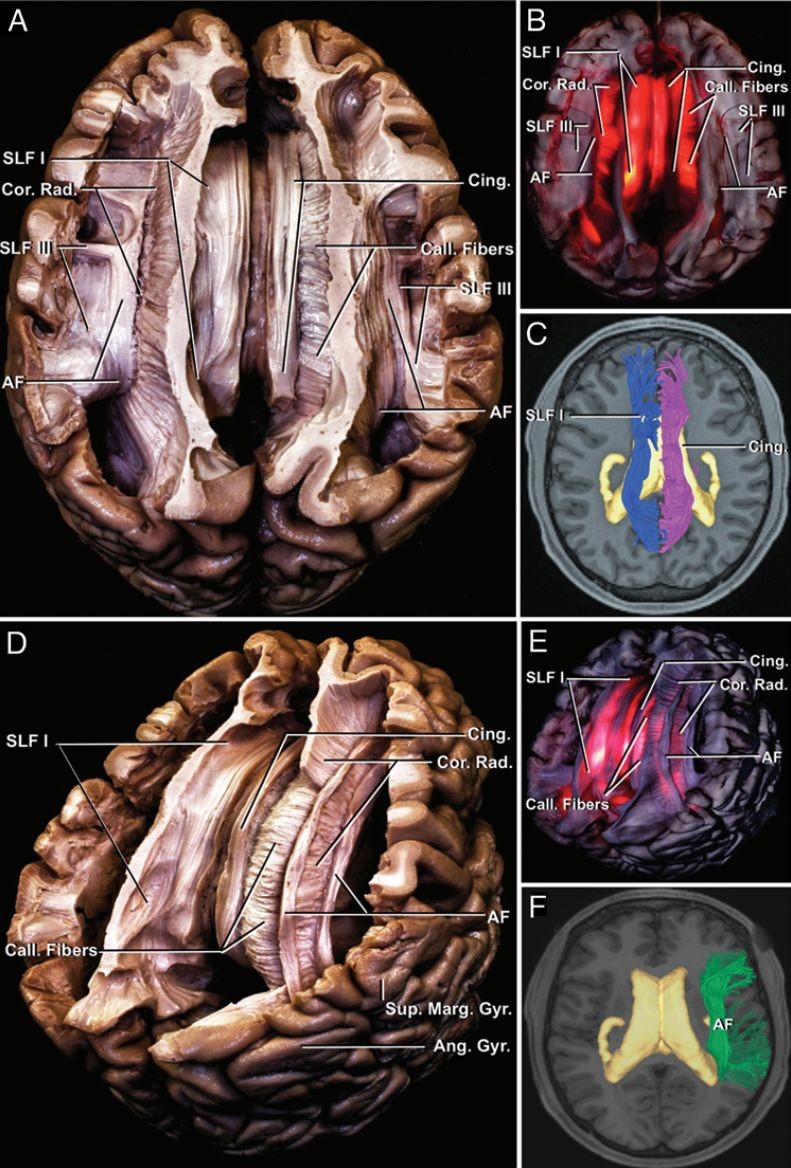

神外专题二大脑白质纤维束的解剖意义

基于约束球面反卷积扩散磁共振的脑白质解剖图谱 - 知乎